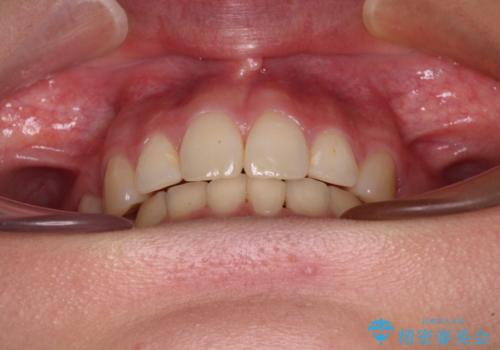

デコボコで飛び出した前歯 ワイヤー装置による抜歯矯正

矯正治療前の咬み合わせで、前歯がすり減ってしまい、歯列が整ったときに先端がガタガタになってしまったため、矯正治療後に形態修正を行いました。